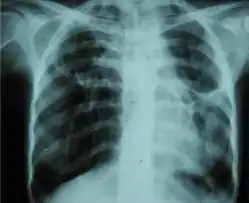

Chest radiograph displaying inhomogeneous opacification of the left half of the chest that is fibrothorax -

A fibrothorax can typically be diagnosed by taking an appropriate medical history in combination with the use of appropriate imaging techniques such as a plain chest X-ray or CT scan.[1] These imaging techniques can detect fibrothorax and pleural thickening that surround the lungs.[11] The presence of a thickened peel with or without calcification are common features of fibrothorax when imaged.[1] CT scans can more readily differentiate whether pleural thickening is due to extra fat deposition or true pleural thickening than X-rays.[1]

If a fibrothorax is severe, the thickening may restrict the lung on the affected side causing a loss of lung volume.[11] Additionally, the mediastinum may be physically shifted toward the affected side.[1] A reduction in the size of one side of the chest (hemithorax) on an X-ray or CT scan of the chest suggests chronic scarring.[9] Signs of the underlying disease causing the fibrothorax are also occasionally seen on the X-ray.[9] A CT scan may show features similar to those seen on a plain X-ray.[11] Lung function testing typically demonstrates findings consistent with restrictive lung disease.[9]